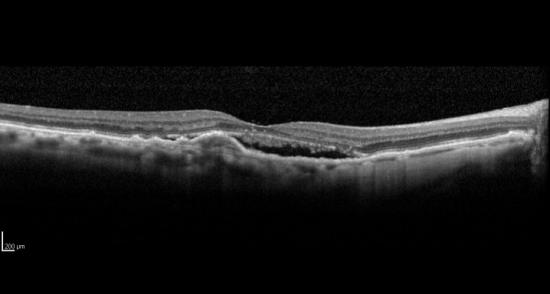

Ensayo clínico en fase IV para evaluar la eficacia de aflibercept en pacientes con degeneración macular asociada a la edad (DMAE) neovascular, sin respuesta óptima a repetidas inyecciones mensuales intravitreas de anti VEGF-A. MACBETH.